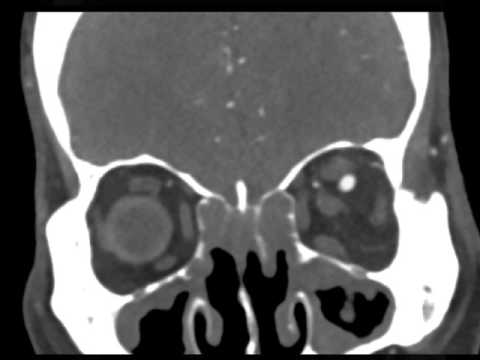

Hellow guys, Welcome to my website, and you are watching Hybrid Technique for Carotid-Cavernous Fistula Embolization. and this vIdeo is uploaded by Brain & Spine Group at 2022-11-05T06:00:40-07:00. We are pramote this video only for entertainment and educational perpose only. So, I hop you like our website.